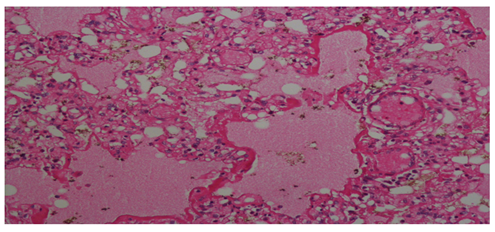

In the histopathological examination report obtained after the autopsy performed in the Morgue Department of Adana Forensic Medicine Group Presidency; ‘Edema, atelectasis, hyaline membranes, haemosiderin-loaded macrophages in large areas in the lungs, acute respiratory distress syndrome compatible appearance (Figure 1). Liver, kidney, spleen, heart, thymus, brain, brain stem and cerebellum congestion are detected and it is stated that the death of the person has an acute respiratory insufficiency syndrome resulting in anaphylactic reaction result related to insect bite. In our case; history, investigation information and histopathological examination were taken into account when ARDS was diagnosed.

Figure 1 Edema, atelectasis, hyaline membranes, haemosiderin-loaded macrophages in large areas in the lungs, acute respiratory distress syndrome (HEX100, HEX200, HEX400).